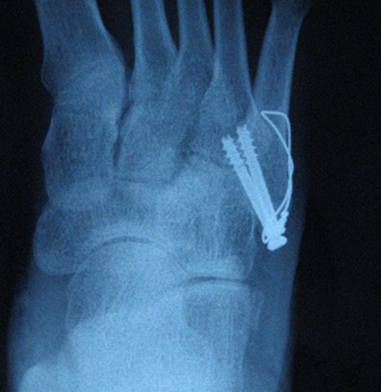

2)新型内固定方式:

• 实心螺钉髓内固定

• 微型钩钢板固定

微型钩钢板固定——一种新的有效手术方法适用于第五跖骨基底部I区和II区骨折(移位﹥2毫米)或者伴有小的粉碎型撕脱骨折块。

第五跖骨基底骨折应用钩钢板固定法治疗更为牢固可靠,且应力性能好;对于粉碎骨折、移位较明显的骨折,钩钢板法尤其具有明显优势,钩钢板的尖头钩可牢固抓持粉碎骨块,实现可靠复位,能更有效缩短患者住院时间、促进骨折愈合、恢复患足功能、促进早期功能锻炼,疗效显著且安全性高,是治疗第五跖骨基底骨折的一种安全有效的方案。

设计:微型管状的钩板的最后一个孔被设计成可充当用于压缩作用的钩,抓粉碎骨折块,防止移位,并且在基底部可以控制旋转稳定。

2.骨折不愈合的处理如骨折超过2个月,因断端分离及骨吸收而出现不愈合,因其骨质发生废用性疏松及断端骨缺损的因素,应使用锁定接骨板螺钉以达到坚强固定的目的,同时应根据情况进行断端植骨以促进骨折愈合。